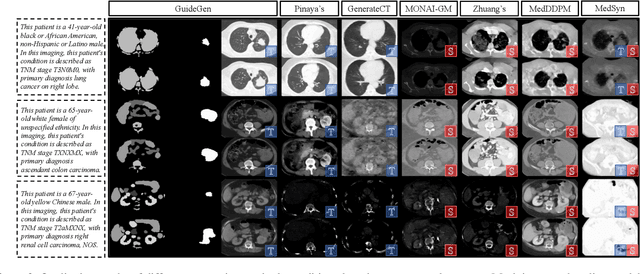

Abstract:The annotation burden and extensive labor for gathering a large medical dataset with images and corresponding labels are rarely cost-effective and highly intimidating. This results in a lack of abundant training data that undermines downstream tasks and partially contributes to the challenge image analysis faces in the medical field. As a workaround, given the recent success of generative neural models, it is now possible to synthesize image datasets at a high fidelity guided by external constraints. This paper explores this possibility and presents \textbf{GuideGen}: a pipeline that jointly generates CT images and tissue masks for abdominal organs and colorectal cancer conditioned on a text prompt. Firstly, we introduce Volumetric Mask Sampler to fit the discrete distribution of mask labels and generate low-resolution 3D tissue masks. Secondly, our Conditional Image Generator autoregressively generates CT slices conditioned on a corresponding mask slice to incorporate both style information and anatomical guidance. This pipeline guarantees high fidelity and variability as well as exact alignment between generated CT volumes and tissue masks. Both qualitative and quantitative experiments on 3D abdominal CTs demonstrate a high performance of our proposed pipeline, thereby proving our method can serve as a dataset generator and provide potential benefits to downstream tasks. It is hoped that our work will offer a promising solution on the multimodality generation of CT and its anatomical mask. Our source code is publicly available at https://github.com/OvO1111/JointImageGeneration.